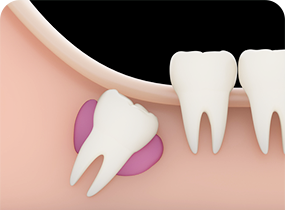

사랑니는,

사랑니 크기에 비해 턱뼈의 공간이 부족한 경우, 사랑니가 올바르게

맹출할 수 없습니다. 이런 경우 사랑니가 누워서 맹출되거나 일부만

맹출되어 여러가지 문제를 야기할 수 있습니다.